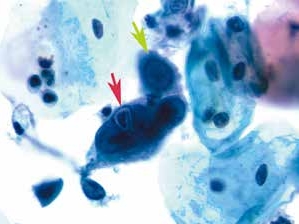

图2-11 真菌:念珠菌属(高倍、液基、巴氏染色)

红箭头指示菌丝(假菌丝);黄箭头指示孢子(大小不一),嗜伊红染。菌丝分节处多见孢子,分支与分支间多呈锐角。

念珠菌属最常见,其感染包括两种:白色念珠菌和光滑念珠菌。宫颈细胞学不容易区分,因为念珠菌的临床治疗均相同,所以鉴别的意义不大,报告查见念珠菌。90%阴道真菌感染为白色念珠菌,其形态特征:分枝状菌丝(假菌丝),实为拉长的孢子,分枝与分枝之间多呈锐角,菌丝分节处多见孢子。小而圆形或椭圆形的孢子(大小不一),嗜伊红染。鳞状上皮细胞可出现反应性胞核稍增大以及核周小空晕,注意与HPV感染的挖空细胞区别。鳞状上皮细胞的胞质皱褶明显。菌丝表面有一种黏附蛋白,长长的菌丝将鳞状上皮细胞黏附成团或成串,酷似土耳其人的串烤牛柳(shishkabob)。

鉴别:丝状黏液、退变精子、空气污染的念珠菌。空气污染的念珠菌有真菌丝,多呈嗜碱性,有分枝,菌丝粗大,但不分节,无孢子。